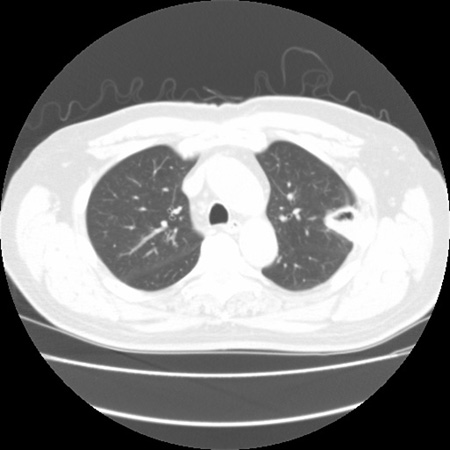

Signo de "halo" en la aspergilosis pulmonar temprana

De la colección del Dr. P. Chandrasekar; utilizada con autorización

Ver esta imagen en el contexto de la/s siguiente/s sección/es: